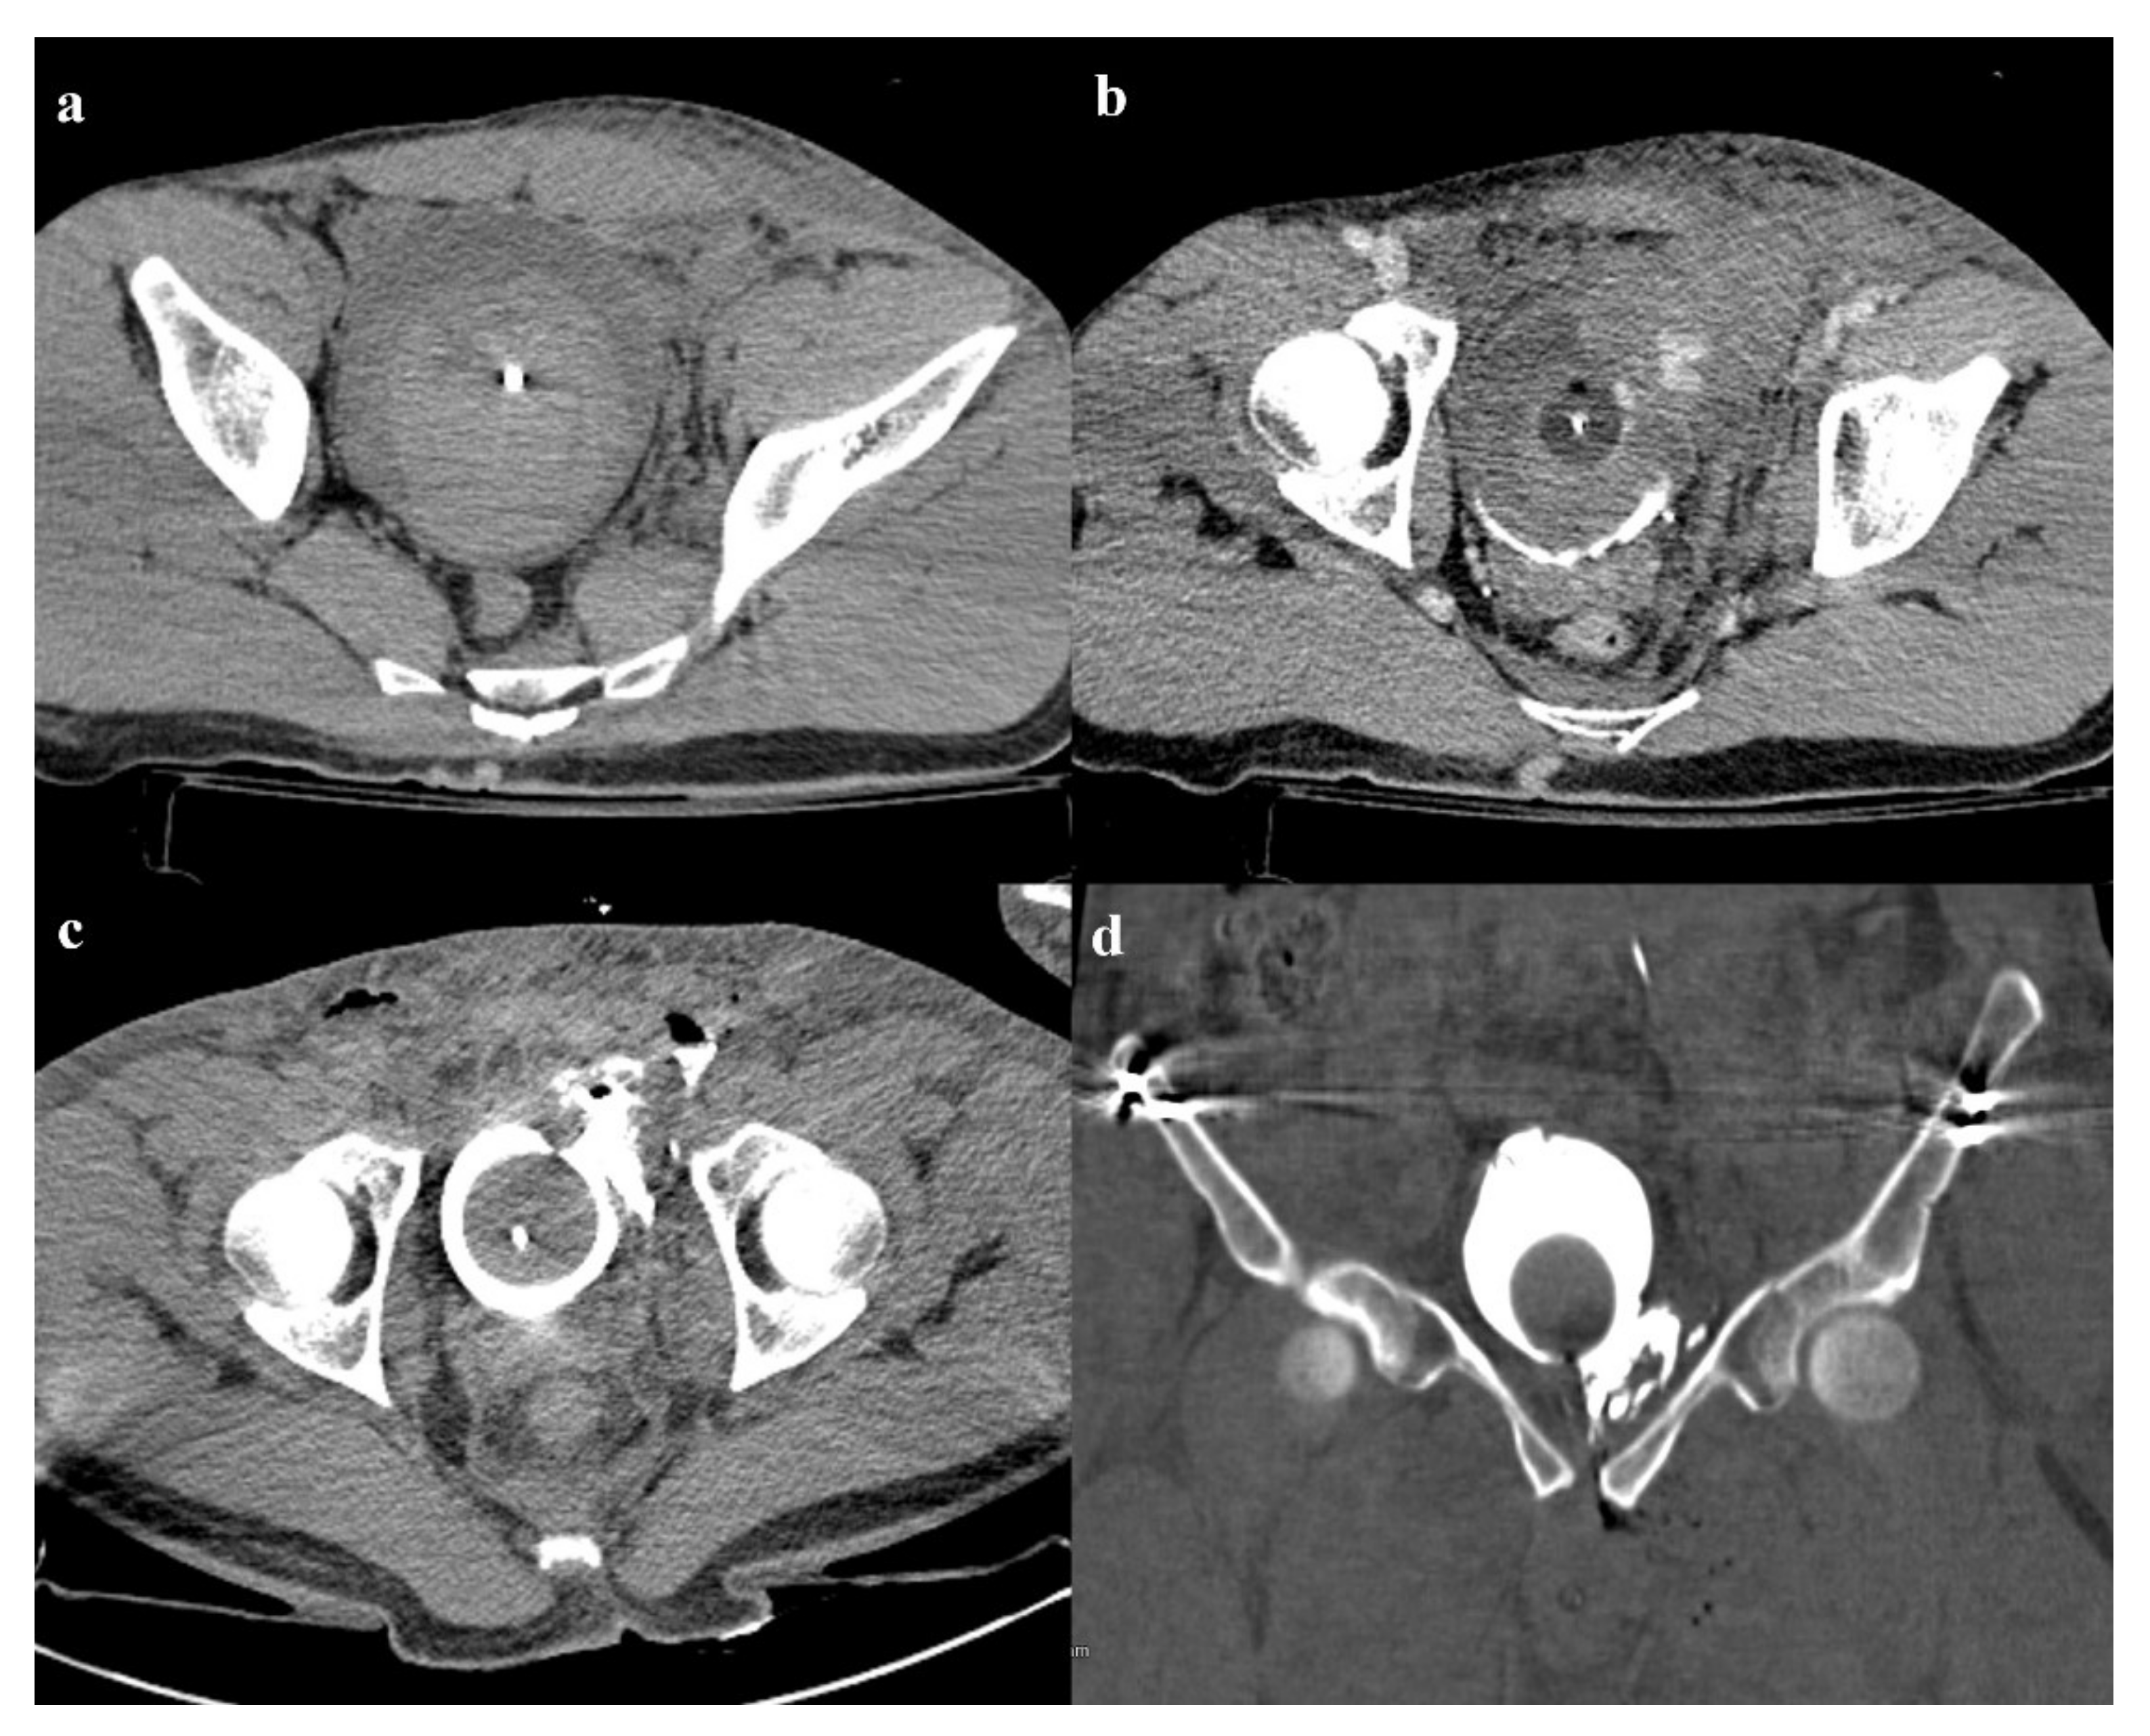

6.2. Bladder and Urethral Complications

- Power, N.; Ryan, S.; Hamilton, P. Computed tomographic cystography in bladder trauma: Pictorial essay. J. Assoc. Can. Radiol. 2004, 55, 304–308. [Google Scholar]

- Vaccaro, J.P.; Brody, J.M. CT cystography in the evaluation of major bladder trauma. Radiographics 2000, 20, 1373–1381. [Google Scholar] [CrossRef] [Green Version]

- Quagliano, P.V.; Delair, S.M.; Malhotra, A.K. Diagnosis of blunt bladder injury: A prospective comparative study of computed tomography cystography and conventional retrograde cystography. J. Trauma 2006, 61, 410–421. [Google Scholar] [CrossRef]

- Trinci, M.; Cirimele, V.; Cozzi, D.; Galluzzo, M.; Miele, V. Diagnostic accuracy of pneumo-CT-cystography in the detection of bladder rupture in patients with blunt pelvic trauma. Radiol. Med. 2020, 125, 907–917. [Google Scholar] [CrossRef]